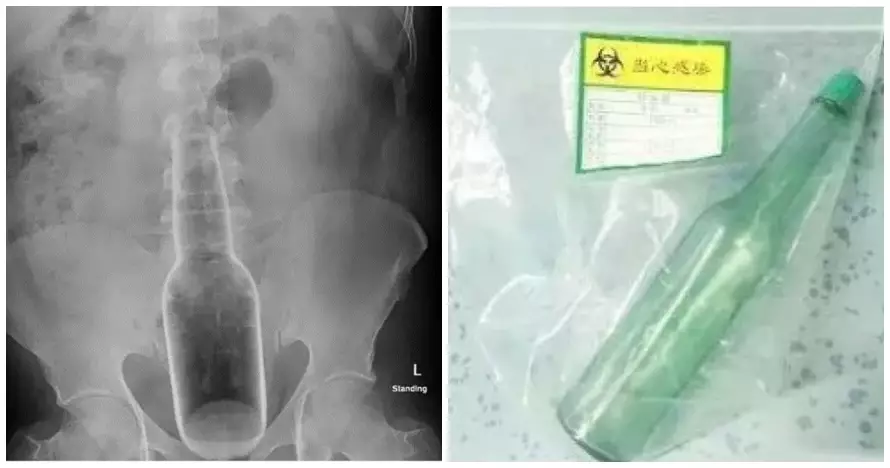

Dilansir brilio.net dari metro.co.uk, Minggu (22/12), saat sedang asyik-asyiknya menggaruk, tanpa sadar botol itu malah masuk ke anus pria ini seutuhnya. Pria ini kemudian pergi ke rumah sakit dan mengeluh kesakitan di bagian perutnya. Usai dilakukan pemeriksaan, ditemukan botol selebar 5 centimeter bersarang di posteriornya.

Ahli Gastroenterologi, Dr Lin Jun yang melakukan operasi anal itu, merilis foto-foto hasil operasi yang dilakukan di rumah sakit di Provinsi Guangdong, China. Pada operasi itu sang dokter mengeluarkan botol deodoran yang panjangnya 17 centimeter dan lebar 5 centimeter dari anus pria tersebut.

foto: metro.co.uk

Dijelaskan oleh Dr Lin Jun, pasiennya itu mengaku kalau sedang menggaruk anusnya dengan botol deodoran karena gatal. Namun secara tidak sadar, botol itu kemudian masuk dan naik ke rektum pria 60 tahun itu.